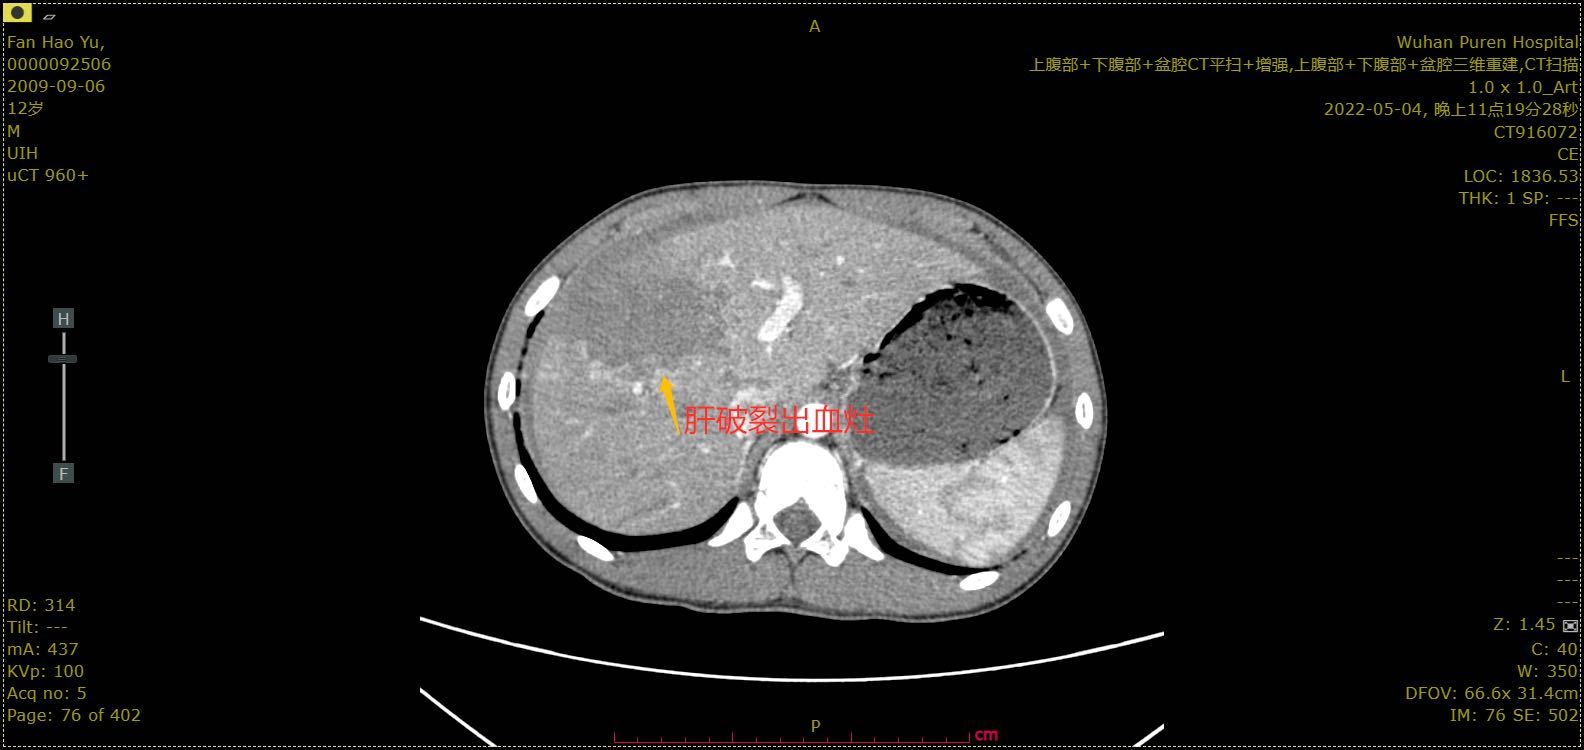

追问下涛涛告诉医生,自行车撞到时,他的右上腹被对方自行车的车把手顶了一下,到现在还隐隐作痛。在医生的建议下,父母带着涛涛做了一个胸腹部的增强CT,结果让家属惊出一身冷汗:肝脏破裂,腹腔大量积血。

增强ct显示肝脏破裂出血灶。